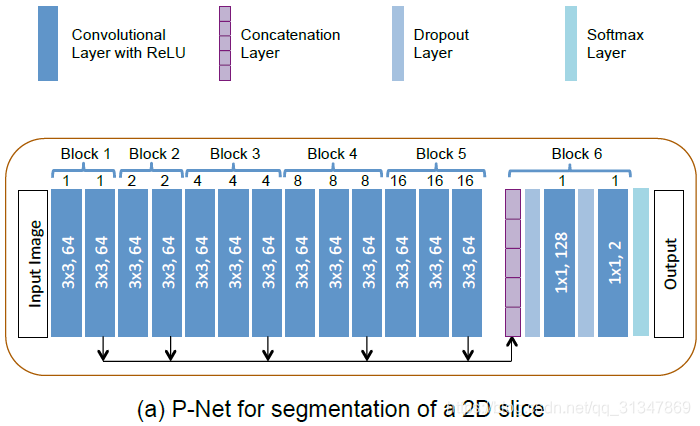

对于 2D 图像,采用 P-Net 做基于 bbox 的二值分割。

P-Net:《DeepIGeoS: A Deep Interactive Geodesic Framework for Medical Image Segmentation》, TPAMI 2018

网络结构:

1)采用了 dilated convolution(空洞卷积/膨胀卷积/带孔卷积)保存图像分辨率,避免细节损失;

2)网络包括 6 个 block,receptive field 为 181x181;

3)前 5 个 block 的 dilation parameter 分别为 1、2、4、8、16,这样就可以从不同的尺度上提取特征;

4)卷积层采用 ReLu 激活函数;

5)前 5 个 block 提取的特征连接后输入第 6 个 block,block 6 可以看作一个分类器;

6)最后一层为 softmax layer,得到概率输出;

Dilated Convolution:《Multi-Scale Context Aggregation by Dilated Convolutions》,ICLR 2016

测试阶段:

根据特定图像对训练得到的模型进行 fine-tuning,更新 CNN 模型参数。为了保证效率和对用户操作快速做出相应,仅 fine-tuning 分类器(block 6)的参数。